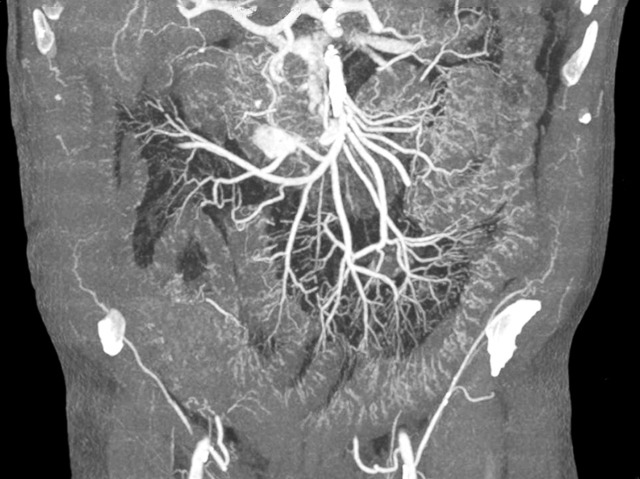

An autopsy is often performed when the cause of someone’s death is unclear – but dissecting the body can be distressing to relatives and is also costly. An alternative is a ‘virtual autopsy’ – marker fluid is injected into an artery and pumped around the body, so that signs of damaged or diseased tissue show up on a scan. The accuracy of this technique is steadily improving. In a recent experiment using a new type of high-contrast marker fluid and computer-enhanced X-ray scanning, the cause of death was correctly diagnosed in 19 out of 20 heart patients. Using this method, even tiny blood vessels buried deep inside the body become visible – in this image of the lower abdomen, they appear as a feathery corona of wispy lines around the large blood vessels.